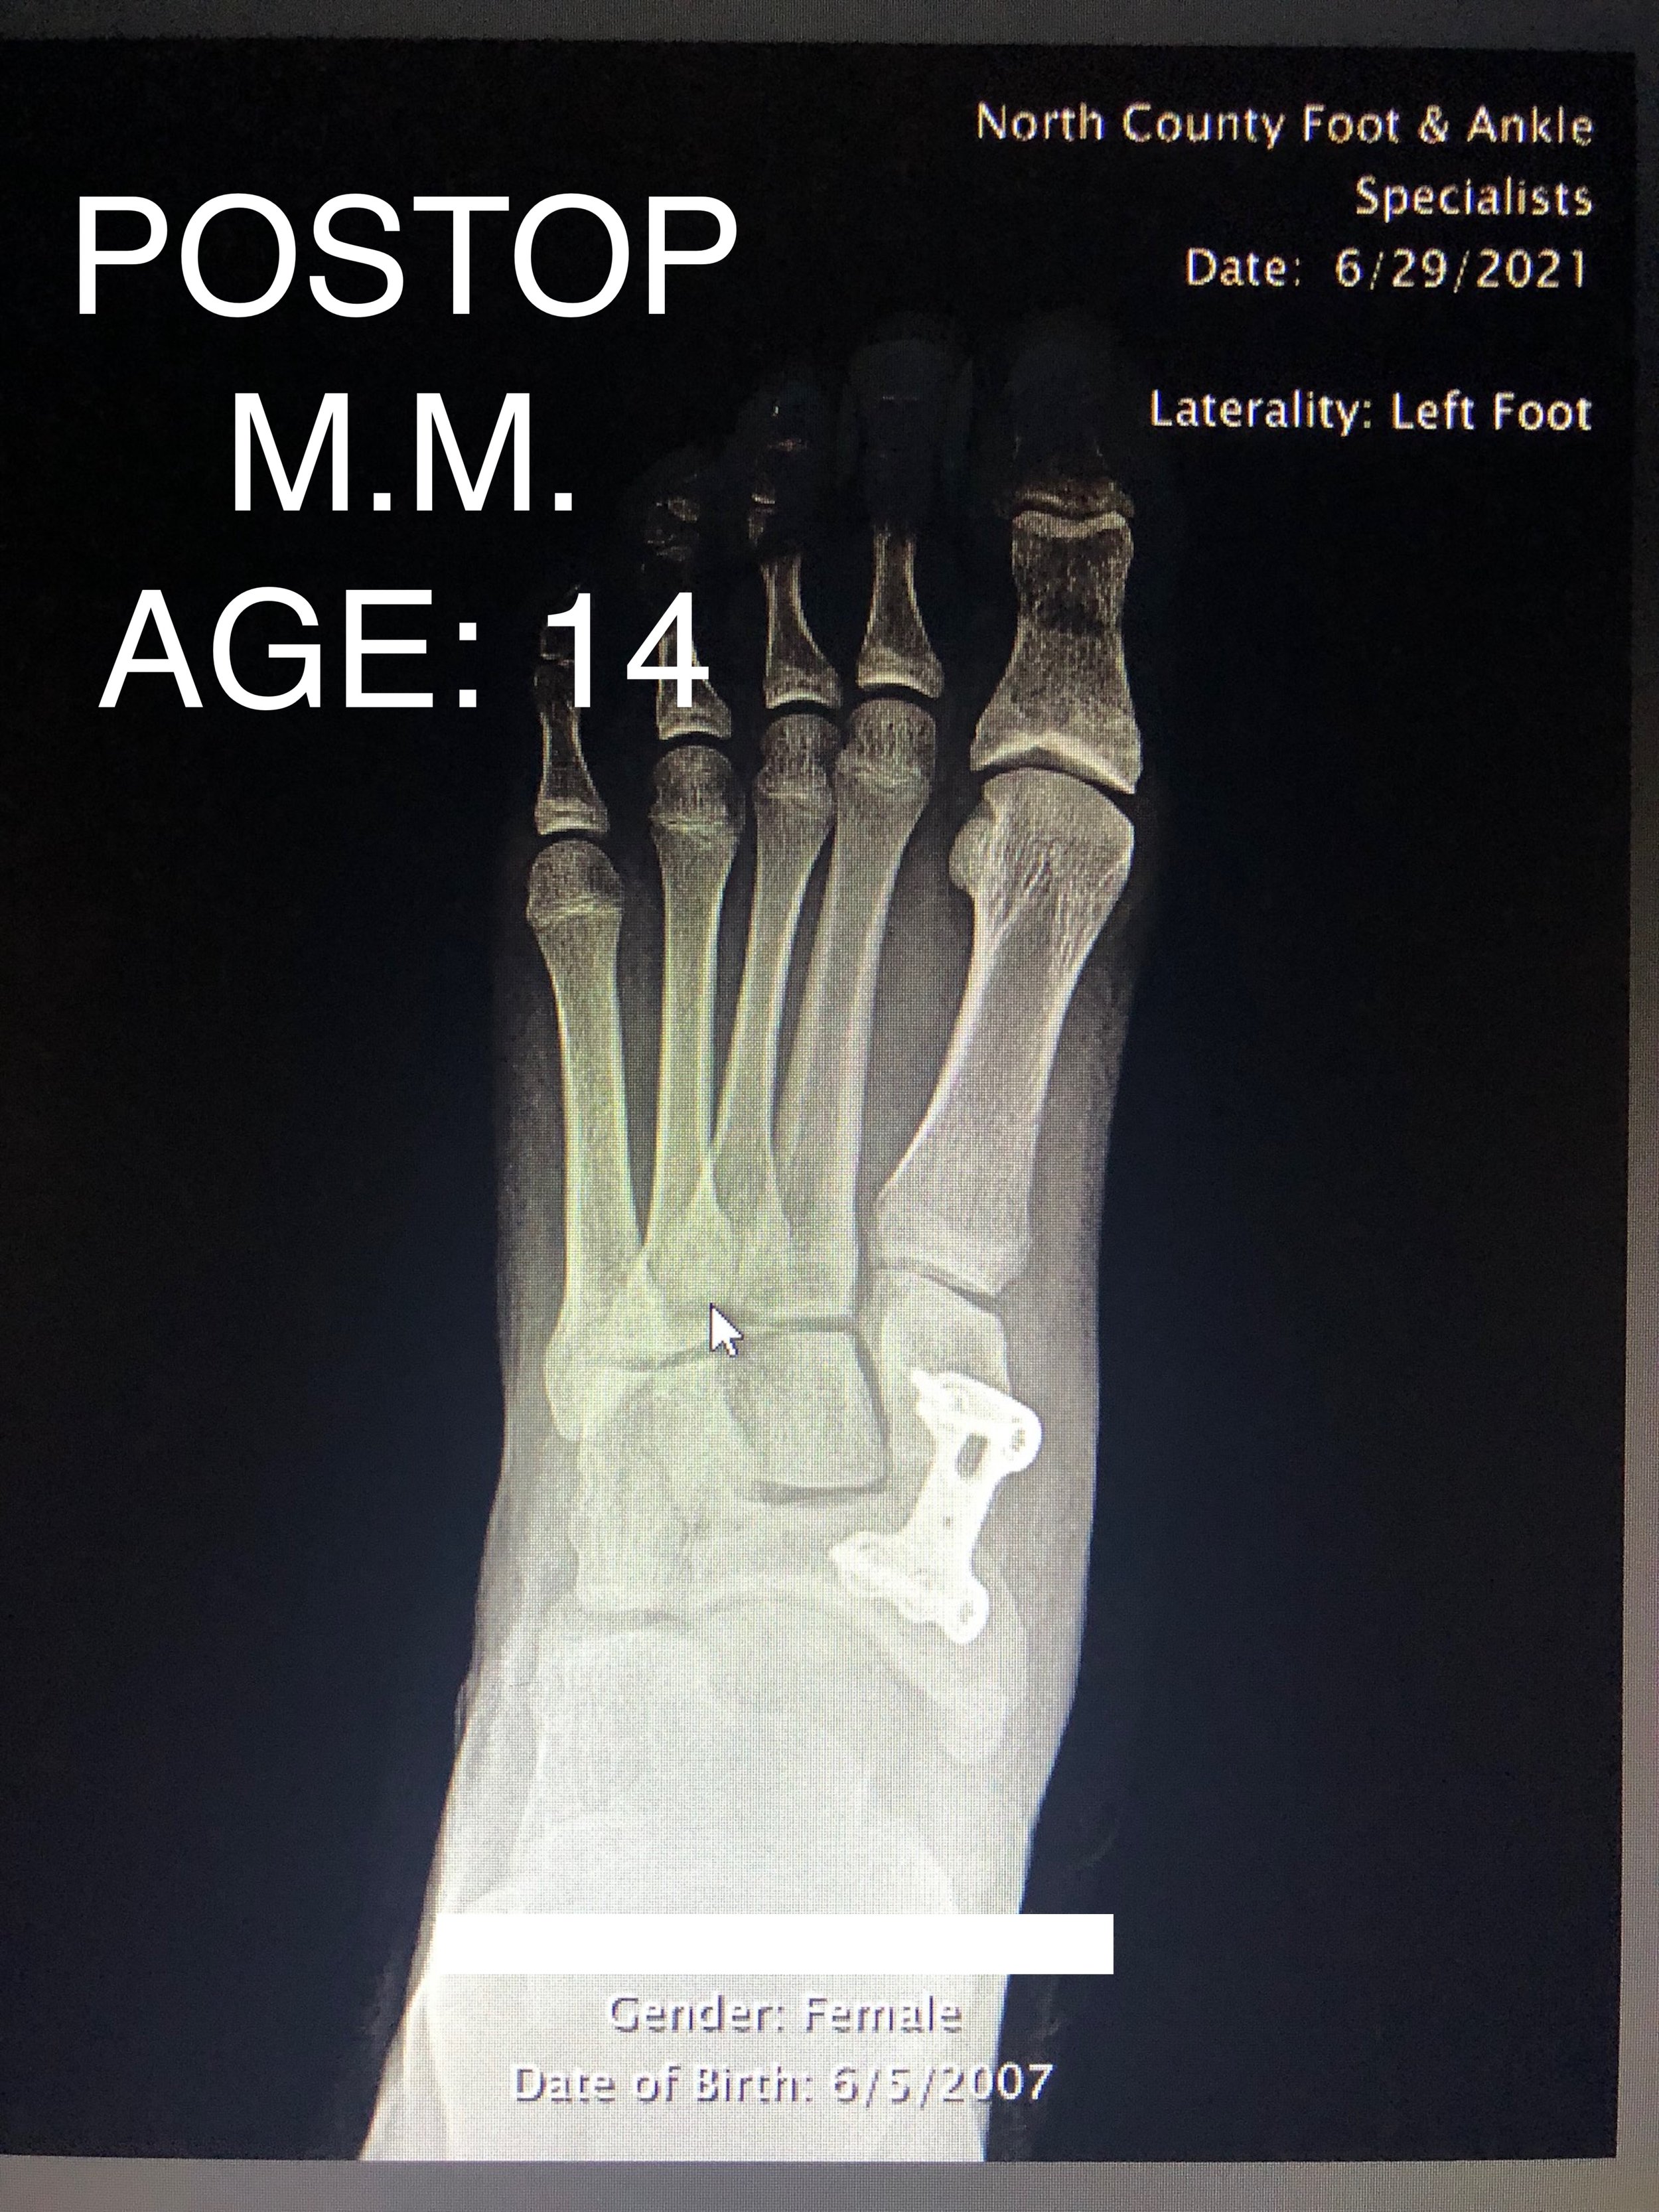

LAPIDUS